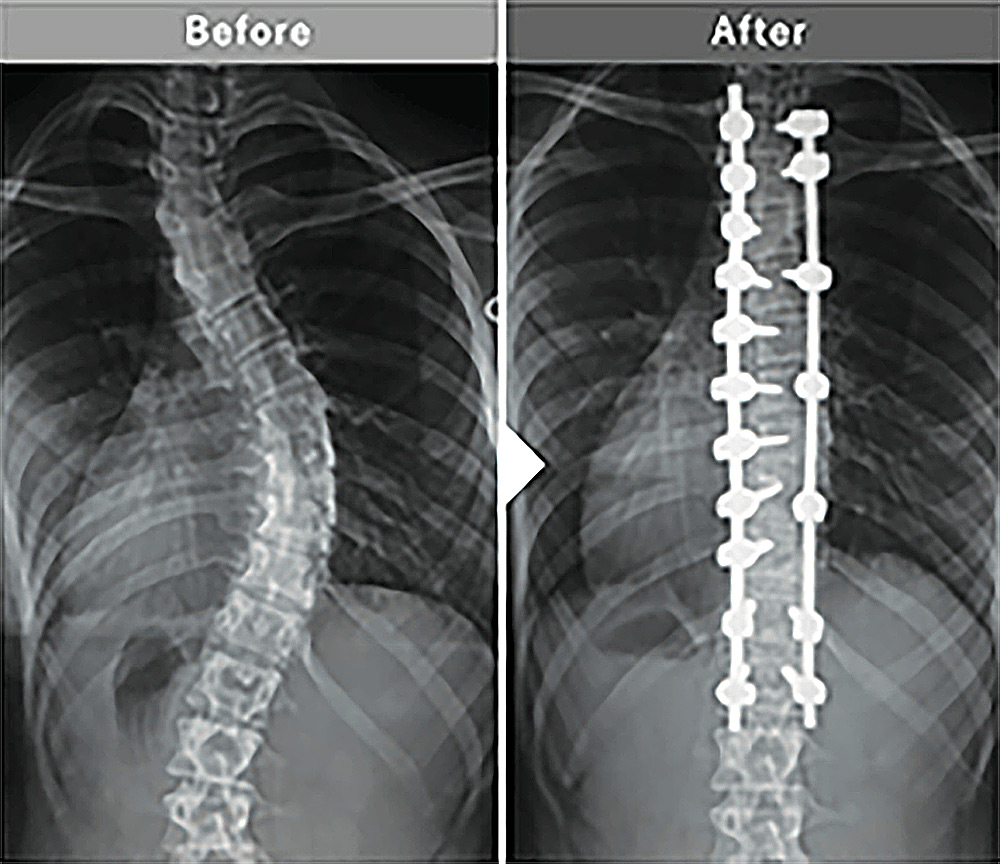

インストゥルメンテーション手術など従来の外科手術と比較して、用いられるスクリューを入れる位置が正確に確認できるようになりました。成人脊柱変形の手術など、スクリューを入れる位置が細く狭い場合などは医師側もかなりの神経を使っていましたが、O-armナビゲーションシステムによって安全に誘導され、成人脊柱変形や側弯症などの矯正固定手術がより安全にできるようになり、患者様の手術後の様子も大きく改善されたと感じます。

矯正固定手術

成人脊柱変形や側弯症に対する広範囲の矯正固定手術